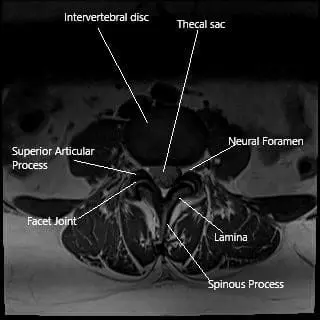

MRI axial section showing the facet joint.

Facet joints connect the vertebrae at the back of the spine and allow for smooth movement. They are surrounded by a capsule that produces synovial fluid—a lubricant that helps the joints move easily.

The facet joints are located behind each vertebra and guide motion in the spine. Each joint has smooth cartilage and is enclosed by a capsule filled with synovial fluid for lubrication.